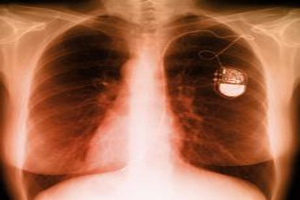

#5 Pace-Maker

Accident causer: Wilson Greatbatch

An Assistant professor’s device tampering lead to one of the greatest technological invention in surgical field- pace-maker for the human heart. Wilson Greatbatch was working on a device that could record fast heartbeats. While designing the circuit for his experiment, Wilson reached for the tool box and instead of pulling out a 10,000-ohm resistor, he accidently picked out the 1-megaohm variety. This caused the circuit to act differently. Instead of recording fast heartbeats, the circuit pulsed for exactly 1.8 milliseconds and paused for 1 second; a dead imitation of a human pulse range. Greatbatch immediately started working on the new circuit and developed the first ever pace-maker that proved to save millions of lives.